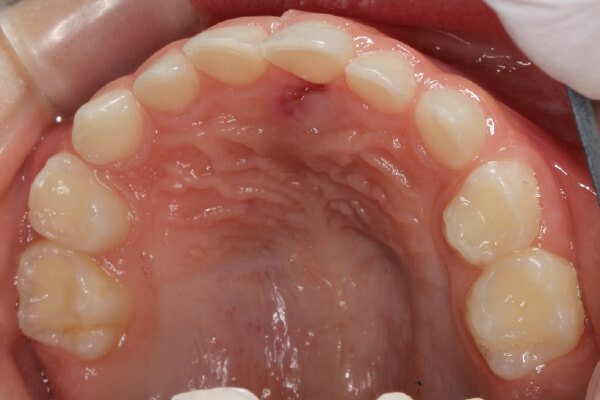

| 主訴 | 過剰歯がある |

|---|---|

| 治療期間 | 1日 |

| 治療費 | 保険診療内 |

| 治療のリスク | 過剰歯の位置によっては一時的な知覚鈍麻、近接する大人の歯(永久歯)に影響が出る場合があるので抜歯後も継続した管理が必要です。 |